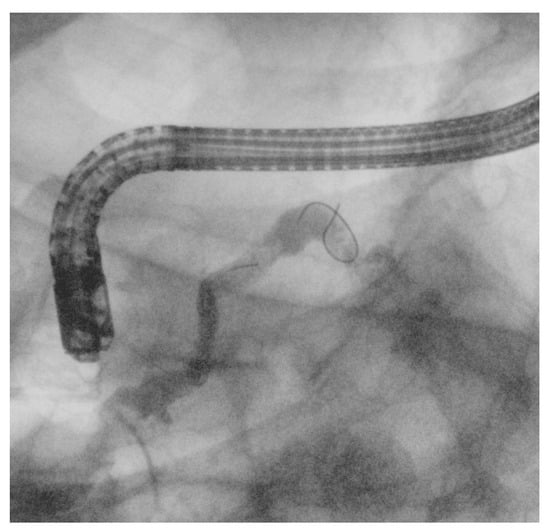

4.3. Other EUS-Guided Procedures

EUS-guided procedures have increasingly adopted lumen-apposing metal stents (LAMSs), revolutionizing various interventions by simplifying access and enhancing procedural efficiency. One of the most significant applications is in the drainage of pancreatic fluid collections or walled-off necrosis, where traditional transmural drainage relied on double-pigtail plastic stents and long guidewires to facilitate device exchanges [2]. The introduction of electrocautery-enhanced LAMSs has minimized the need for guidewires in freehand techniques; however, they remain essential after initial stent deployment. Guidewires can be preloaded into the stent catheter or inserted post-placement to aid further interventions, facilitate LAMS dilation, and enable the coaxial placement of plastic stents [2]. In cases where echoendoscope instability is a concern, placing a guidewire before LAMS deployment can improve stability, reduce technical complications, and serve as a rescue option, such as the “LAMS-in-LAMS” technique [58]. In EUS-guided gastroenterostomy (GEA), LAMSs allow for both direct puncture and guidewire-assisted techniques, though the latter may increase the risk of stent misdeployment [59], due to the potential for guidewire manipulation to displace the bowel [60]. Similarly, EUS-guided choledochoduodenostomy (EUS-CDS) and gallbladder drainage (EUS-GBD) have become effective alternatives for managing biliary obstructions and acute cholecystitis (Figure 9) [61]. LAMSs have significantly improved these procedures, enabling both freehand and over-the-guidewire techniques. Typically, a 19-gauge needle is used for puncture, with guidewires of 0.035-inch or 0.025-inch diameter facilitating stent placement. The 0.025-inch Jagwire Revolution (Boston Scientific, USA) has been noted for its enhanced stiffness, providing a balance between rigidity and maneuverability, which fits for this kind of procedures [34]. In EUS-GBD, the use of a thin 22-gauge EUS-FNA needle can reduce complications like bile leakage, while the 0.018-inch guidewire (e.g., Fielder 18, Asahi Intecc, Japan) has shown promise in improving procedural outcomes [62]. Overall, LAMSs have streamlined EUS-guided procedures, reducing the need for repeated guidewire exchanges while maintaining their role in ensuring technical success.

Figure 9. (a) Guidewire-assisted advancement of a double-pigtail stent through an 8 × 8 mm lumen-apposing metal stent (LAMS) used for choledochoduodenostomy (EUS-CDS) to secure biliary drainage and prevent LAMS obstruction; (b) EUS-guided gallbladder drainage (EUS-GBD) performed using an electrocautery-enhanced lumen-apposing metal stent (LAMS). A 0.035-inch guidewire was used to improve stability and maintain access during deployment.